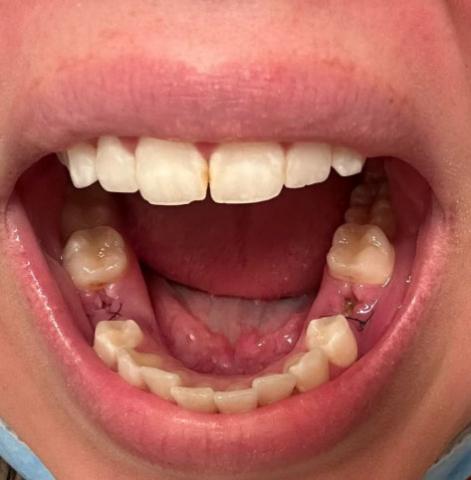

The image shows the lower jaw after recent tooth extractions, with visible sutures on both sides of the lower gum. The extraction sites appear open and healing, with mild redness in the surrounding gum tissue. This is expected shortly after dental surgery, but the area must be monitored closely for signs of infection or delayed healing.

The remaining teeth appear intact, and the soft tissue is in the early healing phase.

This case shows early post-extraction healing with sutures in place, which is normal. Careful monitoring during the first two weeks is critical to prevent infection and support proper bone and gum healing.